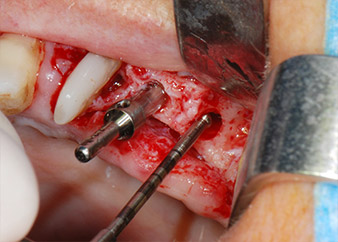

Zunächst wurde in einem Versuch, das Paro-Endo-Problem zu lösen, an der verbleibenden Wurzeloberfläche ein vorsichtiges Debridement mit einem piezochirurgischen Gerät vorgenommen (Piezomed, W&H) (Abb. 4); dann wurde der Apex mit dem gleichen Instrument im Sinne einer WSR abgetragen, um das verbleibende infizierte apikale Gewebe zu entfernen (Abb. 5). Eine retrograde Füllung war nicht notwendig, da die orthograde Füllung gerade revidiert worden war.